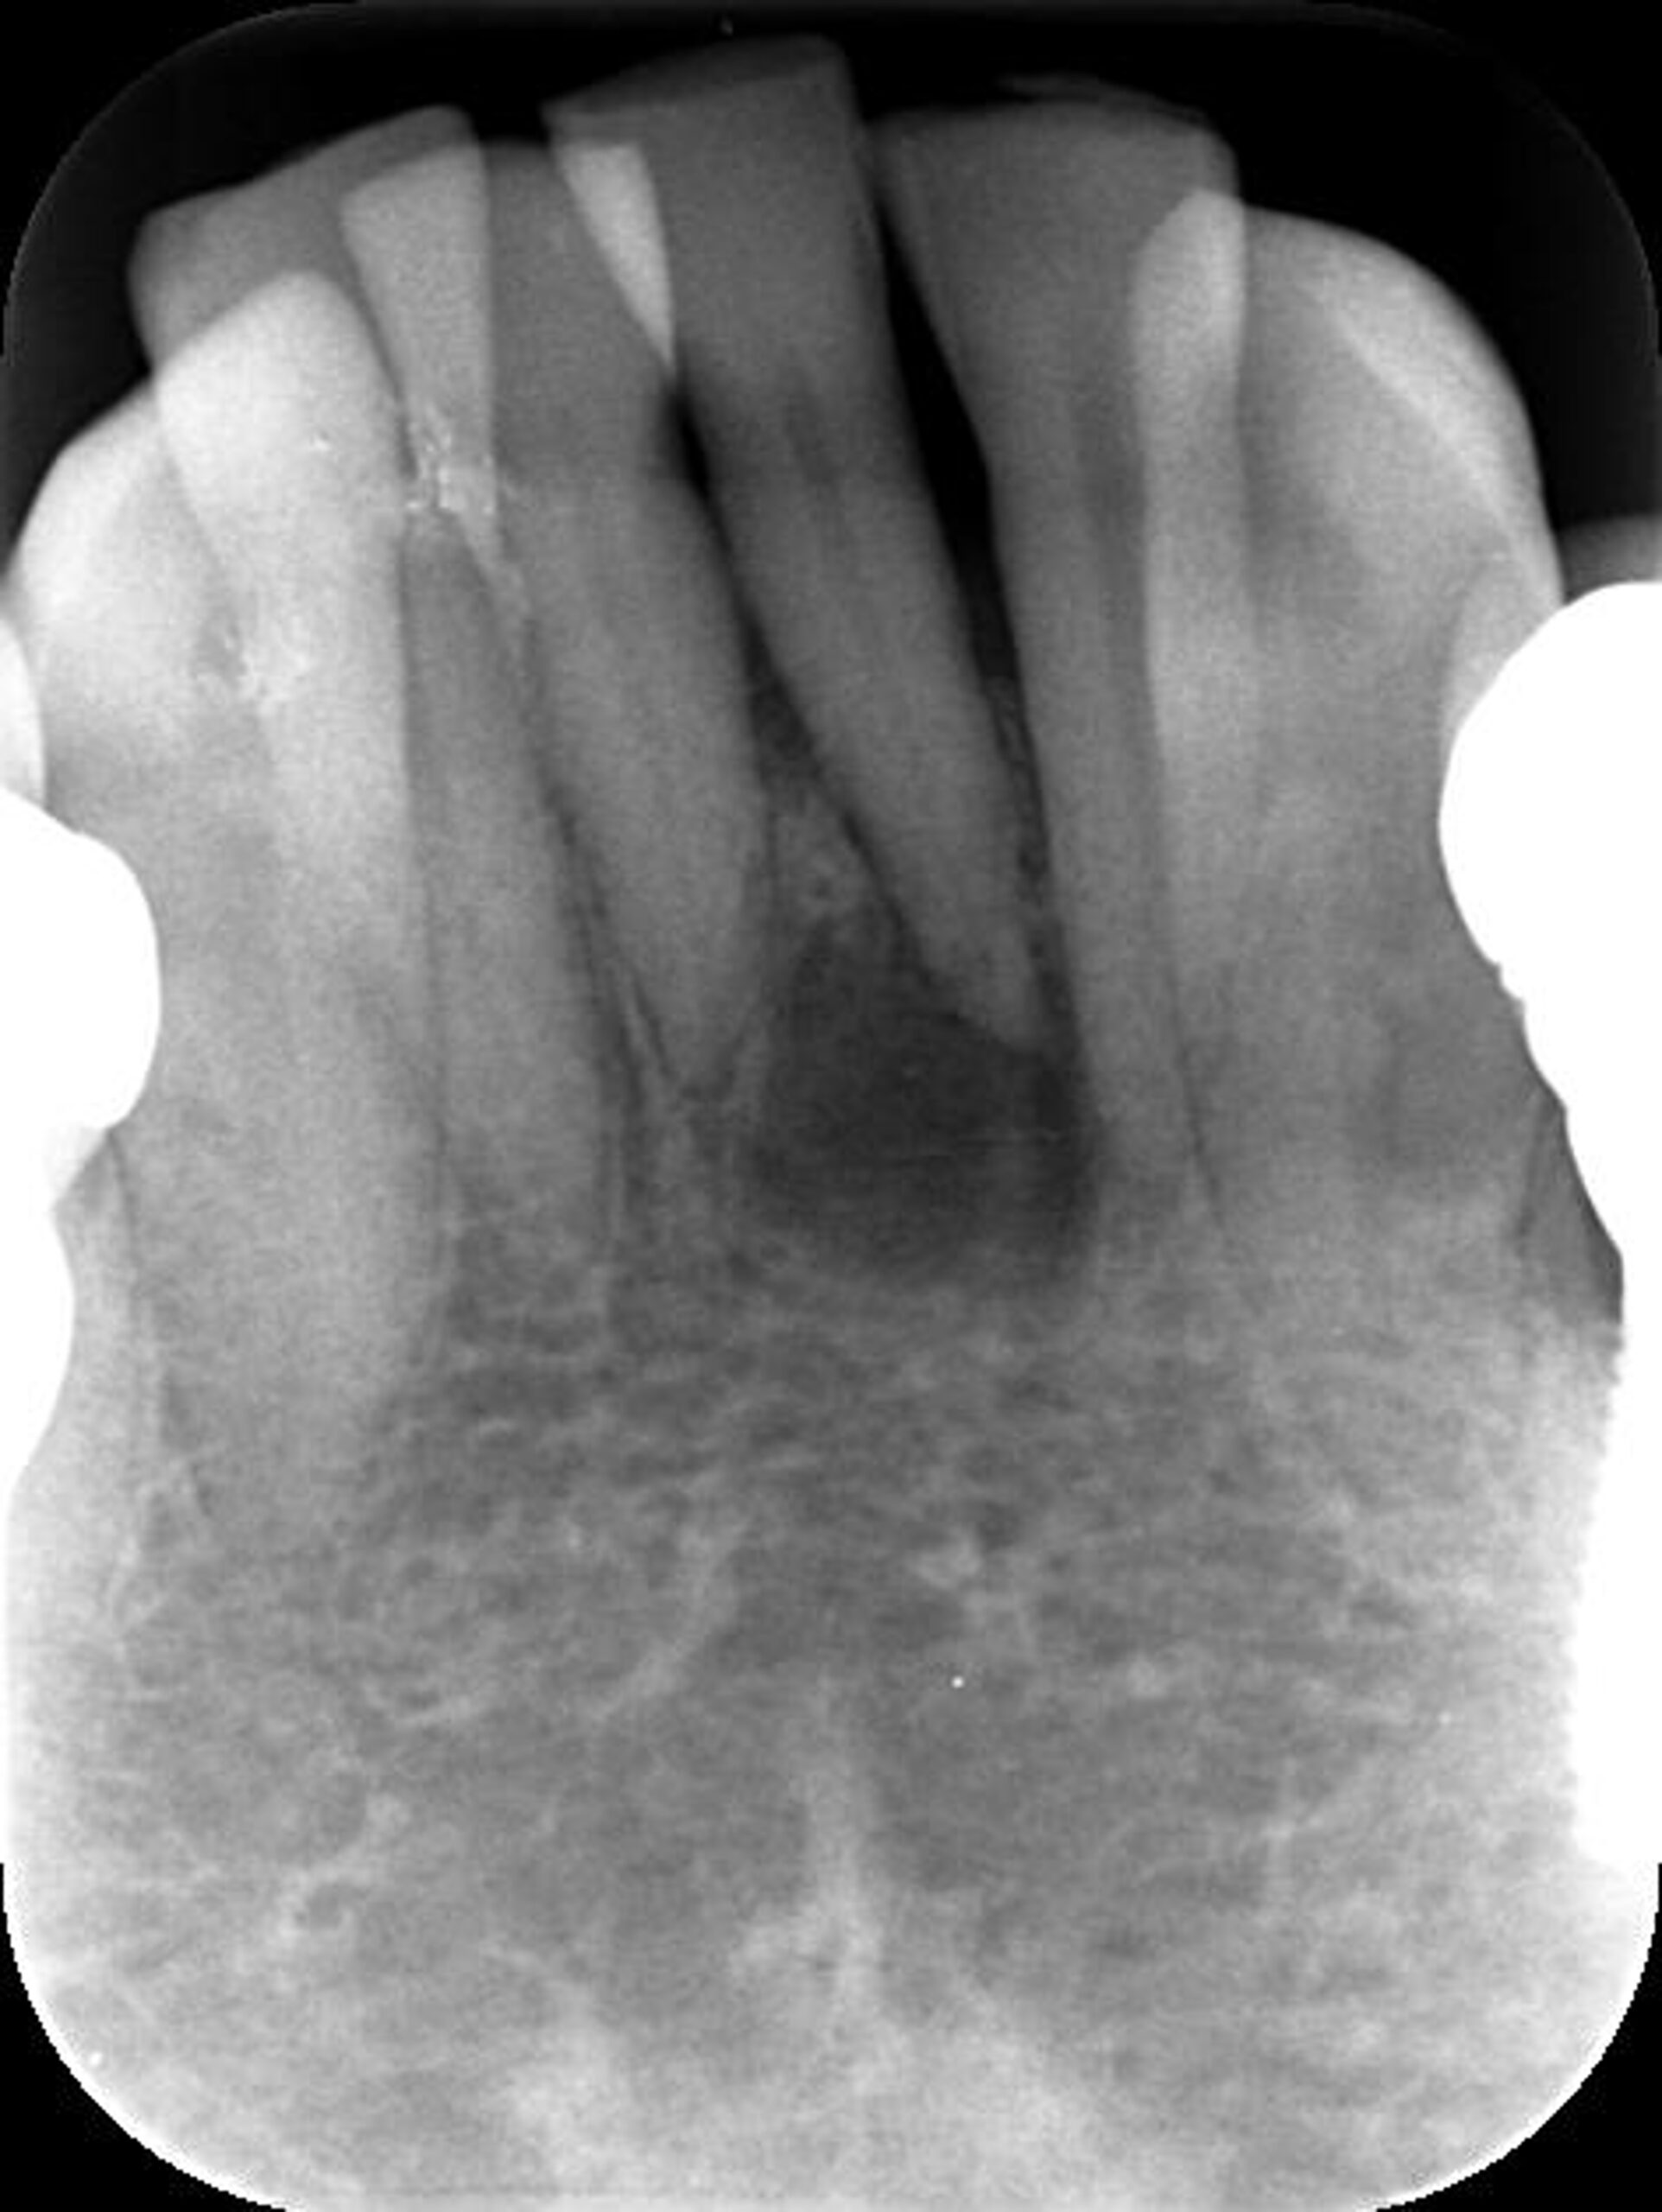

症例4

治療経過

①![]() 術前 |

②![]() 根管治療後3か月経過 |

③![]() 根管治療後1年経過時 |

④![]() 根管治療後2年経過時 |

神経の治療後、①→②→③→④と時間をかけて徐々に治ってくることがあります。

神経の治療は細菌感染を除去する治療です。細菌がいなくなれば、無駄に神経をとらなくても良い歯もあるかもしれません。

レントゲン検査や患者様の訴える症状だけでは神経を残せるかどうかは断定できません。 この方もレントゲン写真上では神経を残せないように見える歯でしたが、治療前に検査を入念に行うことで残せる可能性を見出すことができました。 同じ悩みを抱えた方は是非お気軽にご相談下さい。 |